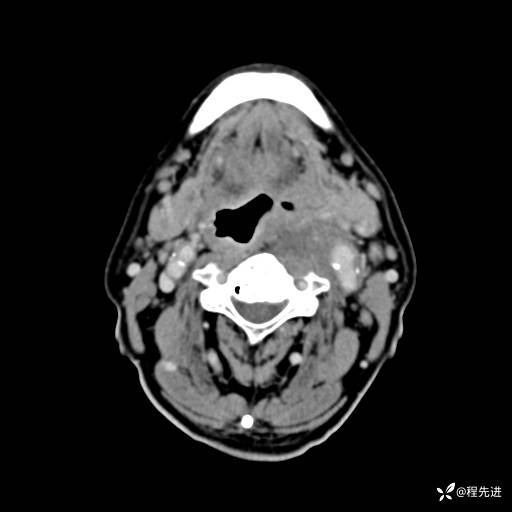

CT增强:

动脉期:

静脉期: